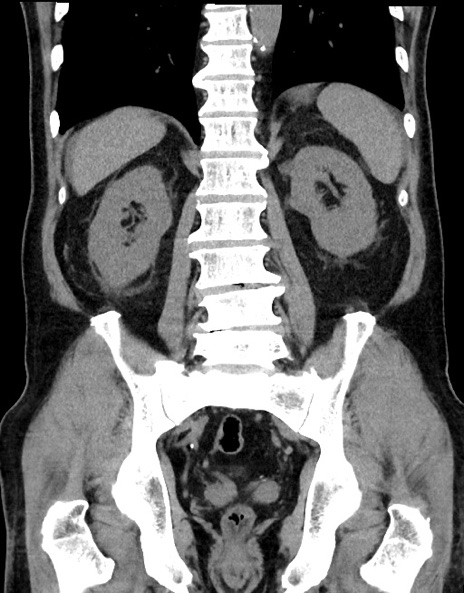

症例15(冠状断像)

【症例】70歳代男性

【主訴】腹痛

【現病歴】今朝から腹痛あり。全体的に痛い。特に左上の方。排ガスが今日はない。冷や汗が出る。

【既往歴】直腸癌術後

【身体所見】左側腹部〜上腹部に圧痛あり。腹膜刺激症状明らかなではない。軽度反跳痛。左下腹部に術後瘢痕あり。

【データ】WBC 7700、CRP 0.02